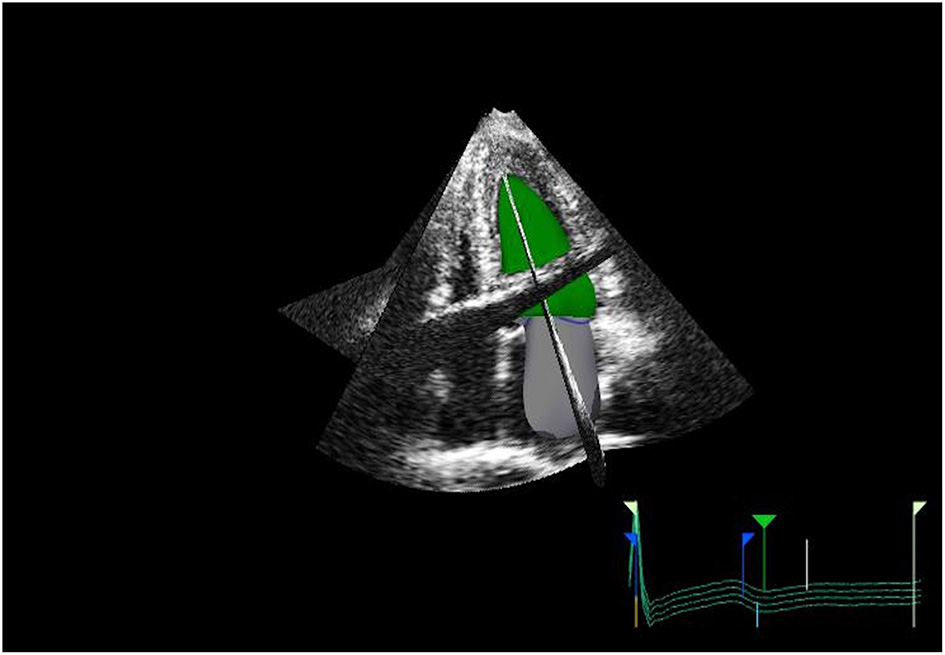

Measurement of LA size is a crucial element of a multiparametric assessment of patients with HF. LA size is measured with M-mode and two-dimensional transthoracic echocardiography (2DE) by evaluating the anteroposterior diameter (4). However, this has proven inaccurate, as the LA does not dilate uniformly. The maximal left atrial volume indexed to the body surface area (LAVi) is the method of choice as it is considered the most accurate. In fact, it is strongly associated with cardiac outcomes (5) and enables risk stratification. The predictive power of LAVi has been enhanced by the advent of three-dimensional echocardiography (3DE) (6, 7), which allows a more precise evaluation of the left atrial volume (LAV) without geometric assumptions and foreshortening (8) (Figure 1). Values from 3DE better correlate with the volume obtained with

Figure 1

3D echo reconstruction of the left atrium (LA) and left ventricle (LV). LA is shown at its end-diastolic phase in order to appreciate left maximal atrial volume.